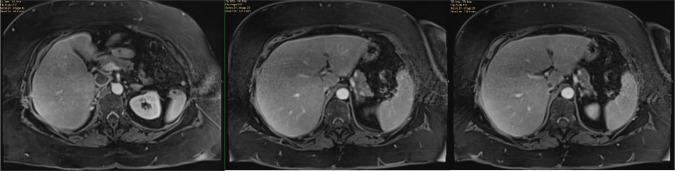

Intraoperative tumor thrombus embolization is a potentially lethal complication during inferior vena cava (IVC) thrombectomy for renal cell carcinoma (RCC). Intraoperative embolization is uncommonly encountered because IVC thrombectomy surgical technique is focused on avoiding this complication. Nonetheless, early recognition of embolization is essential so that emergent management can be instituted. When available, cardiopulmonary bypass (CPB) and embolectomy should be considered the gold standard for the management of intraoperative embolization. Several novel endovascular techniques are also available for selective use. We present the case of a 71-year-old female with a right renal mass and level II (retrohepatic) IVC tumor thrombus. During cytoreductive nephrectomy and IVC thrombectomy, tumor embolization was diagnosed during a period of hypotension based on transesophageal echocardiographic finding of new thrombus within the right atrium. This prompted sternotomy, CPB, and pulmonary artery embolectomy. The patient survived this embolization event and has a complete response to systemic therapy 9 months postoperatively. This case serves as the framework for a discussion on management considerations surrounding intraoperative embolization during IVC thrombectomy.

Abstract Image